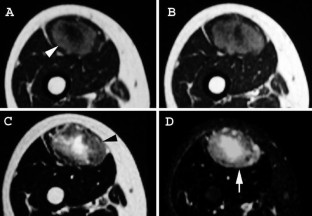

Fig. 1 A, B

Fig. 2